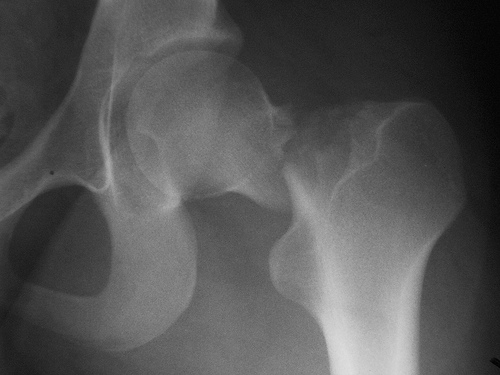

No se está tratando bien la osteoporosis luego de la fractura de cadera

Un estudio encuentra que menos del 10% de los pacientes había iniciado tratamiento para osteoporosis luego de 6 meses de la fractura, a pesar de los beneficios demostrados de los fármacos en esta indicación. JAMA Network Open, 20 de julio de 2018